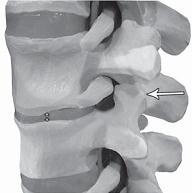

Как вы помните, позвоночно-двигательный сегмент является структурой трёхопорной (межпозвонковый диск и два дугоотростчатых сустава, на которые приходится вся нагрузка от веса вышележащей части тела и мышечных усилий). Чтобы понять суть данного метода, для начала рассмотрим на макете позвоночника, что происходит в процессе вытяжения с межпозвонковым сегментом.

На фото № 4 макета позвоночника наблюдается нормальное взаимоотношение суставных поверхностей в дугоотростчатых суставах.

На фото № 10 макета позвоночника наблюдается нормальное взаимоотношение суставных поверхностей дугоотростчатых суставов, в норме высота межпозвонкового диска и межпозвонковых отверстий.